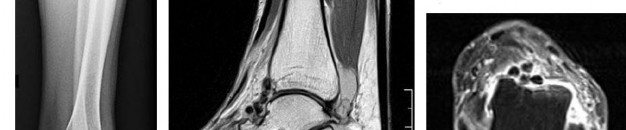

A 15-year-old male presents with deep knee pain awakening him at night. Radiographs show a permeative destructive lesion in the distal femoral metaphysis with a 'sunburst' periosteal reaction and Codman's triangle.

Biopsy confirms high-grade conventional osteosarcoma. What is the most critical prognostic factor for long-term overall survival in this patient?

Explanation

For localized high-grade osteosarcoma, the most important prognostic indicator is the histologic response to neoadjuvant chemotherapy. This is evaluated during the definitive resection. A 'good response' is typically defined as greater than 90% or 99% tumor necrosis. Patients who achieve this level of necrosis have a significantly improved disease-free and overall survival rate compared to 'poor responders' who have extensive viable tumor cells remaining.